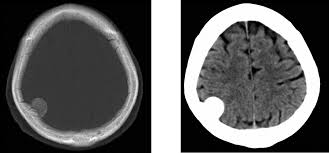

En un estudio de caso-control se exploró la asociación entre el diagnóstico de meningioma que requiere cirugía y el uso previo de anticonceptivos orales que contienen desogestrel o levonorgestrel. Los resultados mostraron un ligero aumento del riesgo de meningioma intracraneal en mujeres que habían usado desogestrel 75 µg durante más de cinco años consecutivos, pero no hubo riesgo en usuarias de levonorgestrel (solo o combinado con estrógeno). BMJ, 11 de junio de 2025.